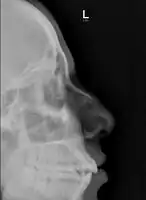

| Plain X-ray showing a nasal fracture | |

The most common causes include assault, trauma during sports, falls, and motor vehicle collisions.[1] Diagnosis is typically based on the signs and symptoms; with plain X-ray rarely of benefit.[1][6] CT scan may be useful if concerns of other fractures or complications are present.[6][4]

Nasal fractures are usually identified visually and through physical examination.[1] Medical imaging is generally not recommended.[1][2] A priority is to distinguish simple fractures limited to the nasal bones (Type 1) from fractures that also involve other facial bones and/or the nasal septum (Types 2 and 3). In simple Type 1 fractures X-Rays supply surprisingly little information beyond clinical examination. However, diagnosis may be confirmed with X-rays or CT scans, and these are required if other facial injuries are suspected.[2]

Nasal bone fracture